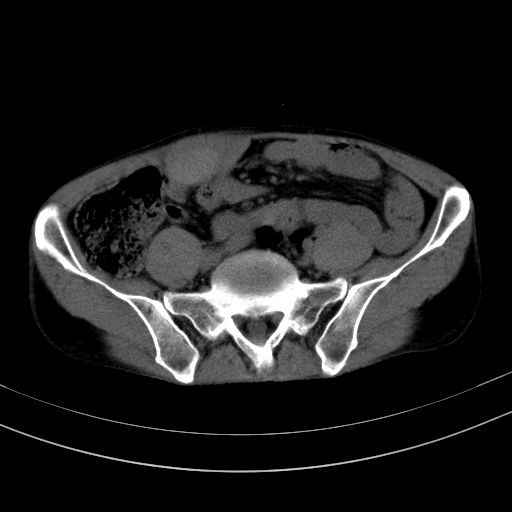

以下是引用37度在2010-1-9 14:37:00的发言:[br]1.双肾囊肿,左肾积水结石,.胆总管轻度扩张;[br]2.病灶在腹膜外,考虑纤维瘤。

以下是引用dyqct在2010-1-9 17:56:00的发言:[br]考虑:1.双肾囊肿,左肾积水结石、旋转不良。[br] 2.右侧腹直肌血肿或纤维瘤。[br]肠道准备不好。做个增强。